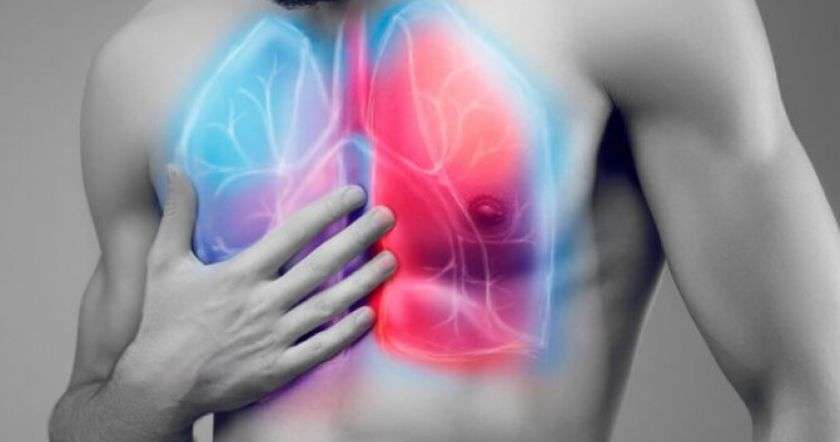

Очень опасным и коварным заболеванием является пневмония. Коварство болезни в том, что человеку порой непросто распознать ее. Чаще всего люди попадают в больницу с уже запущенной стадией.

Из-за того, что нет симптомов болезни, пневмония очень коварная болезнь. Человек может чувствовать себя хорошо, но в один прекрасный день может проснуться со слабостью в теле, кашлем и высокой температурой.

Если плюсом к этим симптомам стало трудно дышать, лицо становится синеватым, а ноги не стоят, то обязательно нужно вызывать скорую помощь и обо всех симптомах сообщаться дежурному врачу.

Обратите внимание на дыхание, на голос. Присутствие сильного кашля, затрудненного дыхания, а также осиплости в горле может говорить и о другой болезни. НО! если вы не можете вдохнуть, вам больно, то это в 90% заболевание легких. Только врач сможет поставить диагноз.